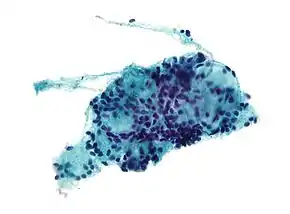

细针穿刺活检是一种可以用來檢測腫瘤和炎症的诊断技術,它也是一種小型外科手术。檢測人員會用皮下注射針穿刺并吸出病人的组织,然後進行染色,之後檢測人員會在顯微鏡下觀察塗色的組織。相對於大型开放式手術活檢,病人無需住院就能進行细针穿刺活检,而且費用更少、更安全、創傷更少,帶來的併發症也更少[1]。不過由於所取组织标本不完全以及量少,因而腫瘤诊断可能會不确切和不可靠。[2][3]美國首例细针穿刺活检於1981年在迈蒙尼德医疗中心完成[4]。